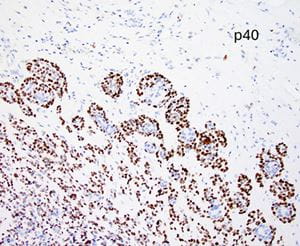

Immunohistochemical findings

Immunohistochemical staining for CK7 and p40 highlights dual cell populations, identifying ductal and myoepithelial components. P16 shows diffuse block positivity. High-risk HPV genotyping by PCR confirms the presence of HR-HPV types 33 or 58.